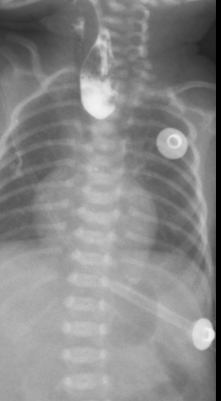

图 1:术前造影片

患者女,4 小时 51 分钟,入院情况:患儿系 4 胎 0 产,胎龄 31+5 周,单胎,因「重度先兆子痫、产前脐血流 S/D 比值高」剖宫产娩出, 有宫内窘迫(具体不详),无胎膜早破。无羊水污染,胎盘正常。Apgar 评分 1 分钟 9 分,5 分钟 9 分,10 分钟 9 分,出生体重 1500 g。出生后无窒息抢救史,4 小时前因「早产儿」在当地医院新生儿科住院,下胃管时受阻考虑食管闭锁,与家属沟通后家属要求转院治疗,遂由我科医护人员转运至我院。急诊以「食道闭锁、早产儿」收住入院。病程中患儿自发病以来,神志清,精神反应欠佳,未开奶,无呕吐、腹胀等症状,胎便已排,小便不详。心脏检查 (常规, 左心功能测定, 室壁运动分析) 彩超检查提示:先天性心脏病:室间隔缺损(肌部);房间隔缺损(中央型);彩色多普勒显示: 室水平左向右分流;房水平左向右分流。2021-08-18 日行胸部 (正位), 腹部 (正位)CR 检查示:先天性食道闭锁;新生儿肺炎较前加重,右肺上叶肺不张;肠管充气减少。上消化道造影 (数字化摄影) 检查示:1. 食道闭锁;2. 新生儿肺炎。不能喂养,有手术指征,完善术前检查,加强呼吸道管理,限期手术。积极完善术前检查,于 2021-08-19 急诊行右后外侧入路经胸膜外食管探查、食管气管瘘修补、食管吻合术。